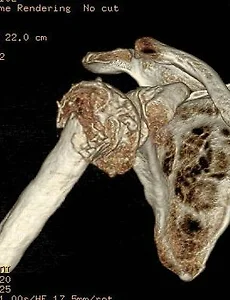

Shoulder61 Proximal humerus fracture Proximal humerus fracture65 years old female patientTripping over a rope Pre-op Post-op Materials : Philos plate(AO synthes) & 2.4 mm mini-plate(AO synthes) 제일 처음 cortical screw를 고정할 위치에 Fx. line이 존재하여미리 2.4 mm mini-plate 로 OR & fixation을 하여어느 정도 stability를 만든 후, Philos plate를 apply 함. 2026. 1. 1. Comminuted clavicle mid-shaft fracture Comminuted clavicle mid-shaft fracture36 years old male patient Pre-op Post-op Materials : AO synthesnew version, 2.7 mm clavicle platelag screw, 2.4 mm mini-screw 쇄골 골절을 쉽게 생각하면 절대 안됩니다 2025. 6. 23. Humerus surgical neck fracture Humerus surgical neck fracture 52 years old female patientSlip down injury in the bath room Pre-op Post-op 2024. 8. 20. Humerus neck fracture(ORIF) Fx humerus neck Lt. 35 years old male patient 자전거 타고 가다가 차와 충돌하여 LOC (+) Pre-op Post-op Product : AO synthes (Philos plate)Delto-pectoral approach 하여 biceps tendon의 just lateral에약간 비스듬히 Philos plate를 대면 정확한 고정이 이뤄집니다. 2024. 6. 22. 어깨의 인대 손상 격렬한 운동을 하다 보면 어깨 관절을 다치기가 아주 쉽습니다. 그러면 어깨 관절에 피하 출혈(멍듦)이 생기기도 합니다. Skin bruise of shoulder joint 어깨 관절의 인대는 상당히 강하며 뼈와 뼈를 연결하는 구조물이기 때문에 우리 몸속 깊숙히 있습니다. 어깨 관절의 인대(ligament) 인대 손상의 확인은 MRI 검사로 합니다. 2021. 11. 6. Frozen shoulder(동결견) 정상적인 어깨 관절은 견갑-흉곽 운동(Scapulo-thoracic motion)에 의해서 복합적으로 이뤄지게 됩니다. 어깨 통증으로 평소 사용하는 앞쪽 근육이 아닌 잘 사용하지 않는 어깨 뒷쪽 근육부터 굳기 시작을 합니다. 그래서 처음에는 어깨의 내회전(열중 쉬어 자세)이 안됩니다. '동결견'은 어떤 이유(당뇨, 경추부 추간판 탈출증, 골절 등)로 인해 '어깨 관절의 운동 범위가 감소한 경우'로 정의 합니다 '동결견'의 병태 생리는 '어깨 관절의 비화농성 염증(non-pyogenic inflammation) 및 관절막의 섬유화(fibrosis)' 입니다 최근에는 '경추부 추간판 탈출증'으로 인한 '이차성 동결견'이 증가하는 양상을 보이고 있습니다 '오십견'이라는 병명은 정확한 병명은 아닙니다 '동결견'.. 2021. 1. 10. Proximal humerus fracture(Hemi-arthropalsty) Proximal humerus fracture 88 years old female patient with severe OA change Pre-op Post-op 2020. 2. 2. Cuff tear arthropathy shoulder Rt. Cuff tear arthropathy shoulder Rt. 70 years old male patient 회전근개 파열 후 오랜 시간이 지나 '관절염'이 발생한 경우입니다. 2019. 11. 18. Calcific tendinitis shoulder both Calcific tendinitis shoulder both 46 years old female patient 2019. 9. 4. 이전 1 2 3 4 ··· 7 다음